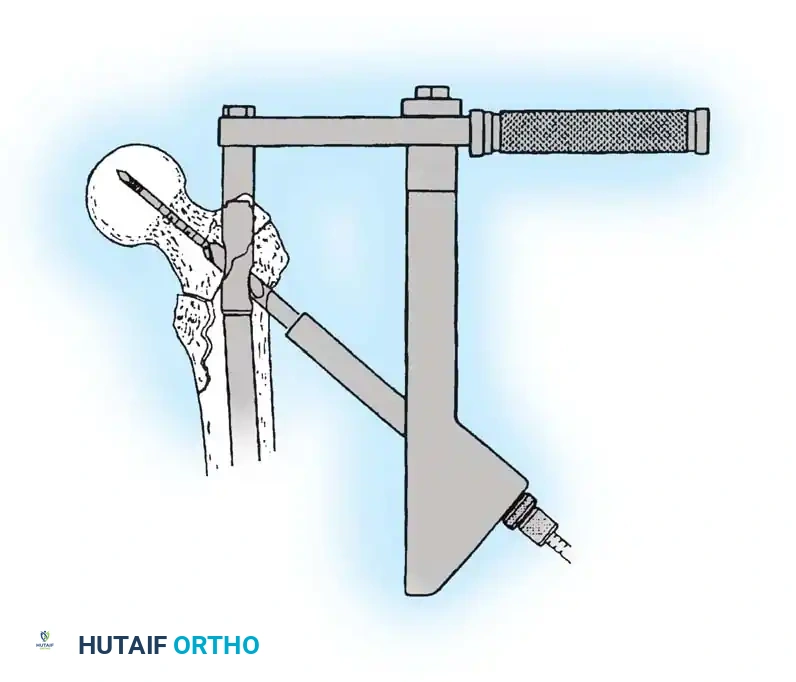

Insertion of the cephalomedullary nail down the femoral shaft. Care must be taken not to distract the fracture site during insertion.

After the nail is seated, the proximal lag screw(s) are inserted through the nail into the femoral head, adhering to the same TAD principles.

Proximal locking of the cephalomedullary nail. The targeting guide ensures accurate trajectory into the femoral neck.

Finally, distal locking screws are placed to control rotation and maintain length.